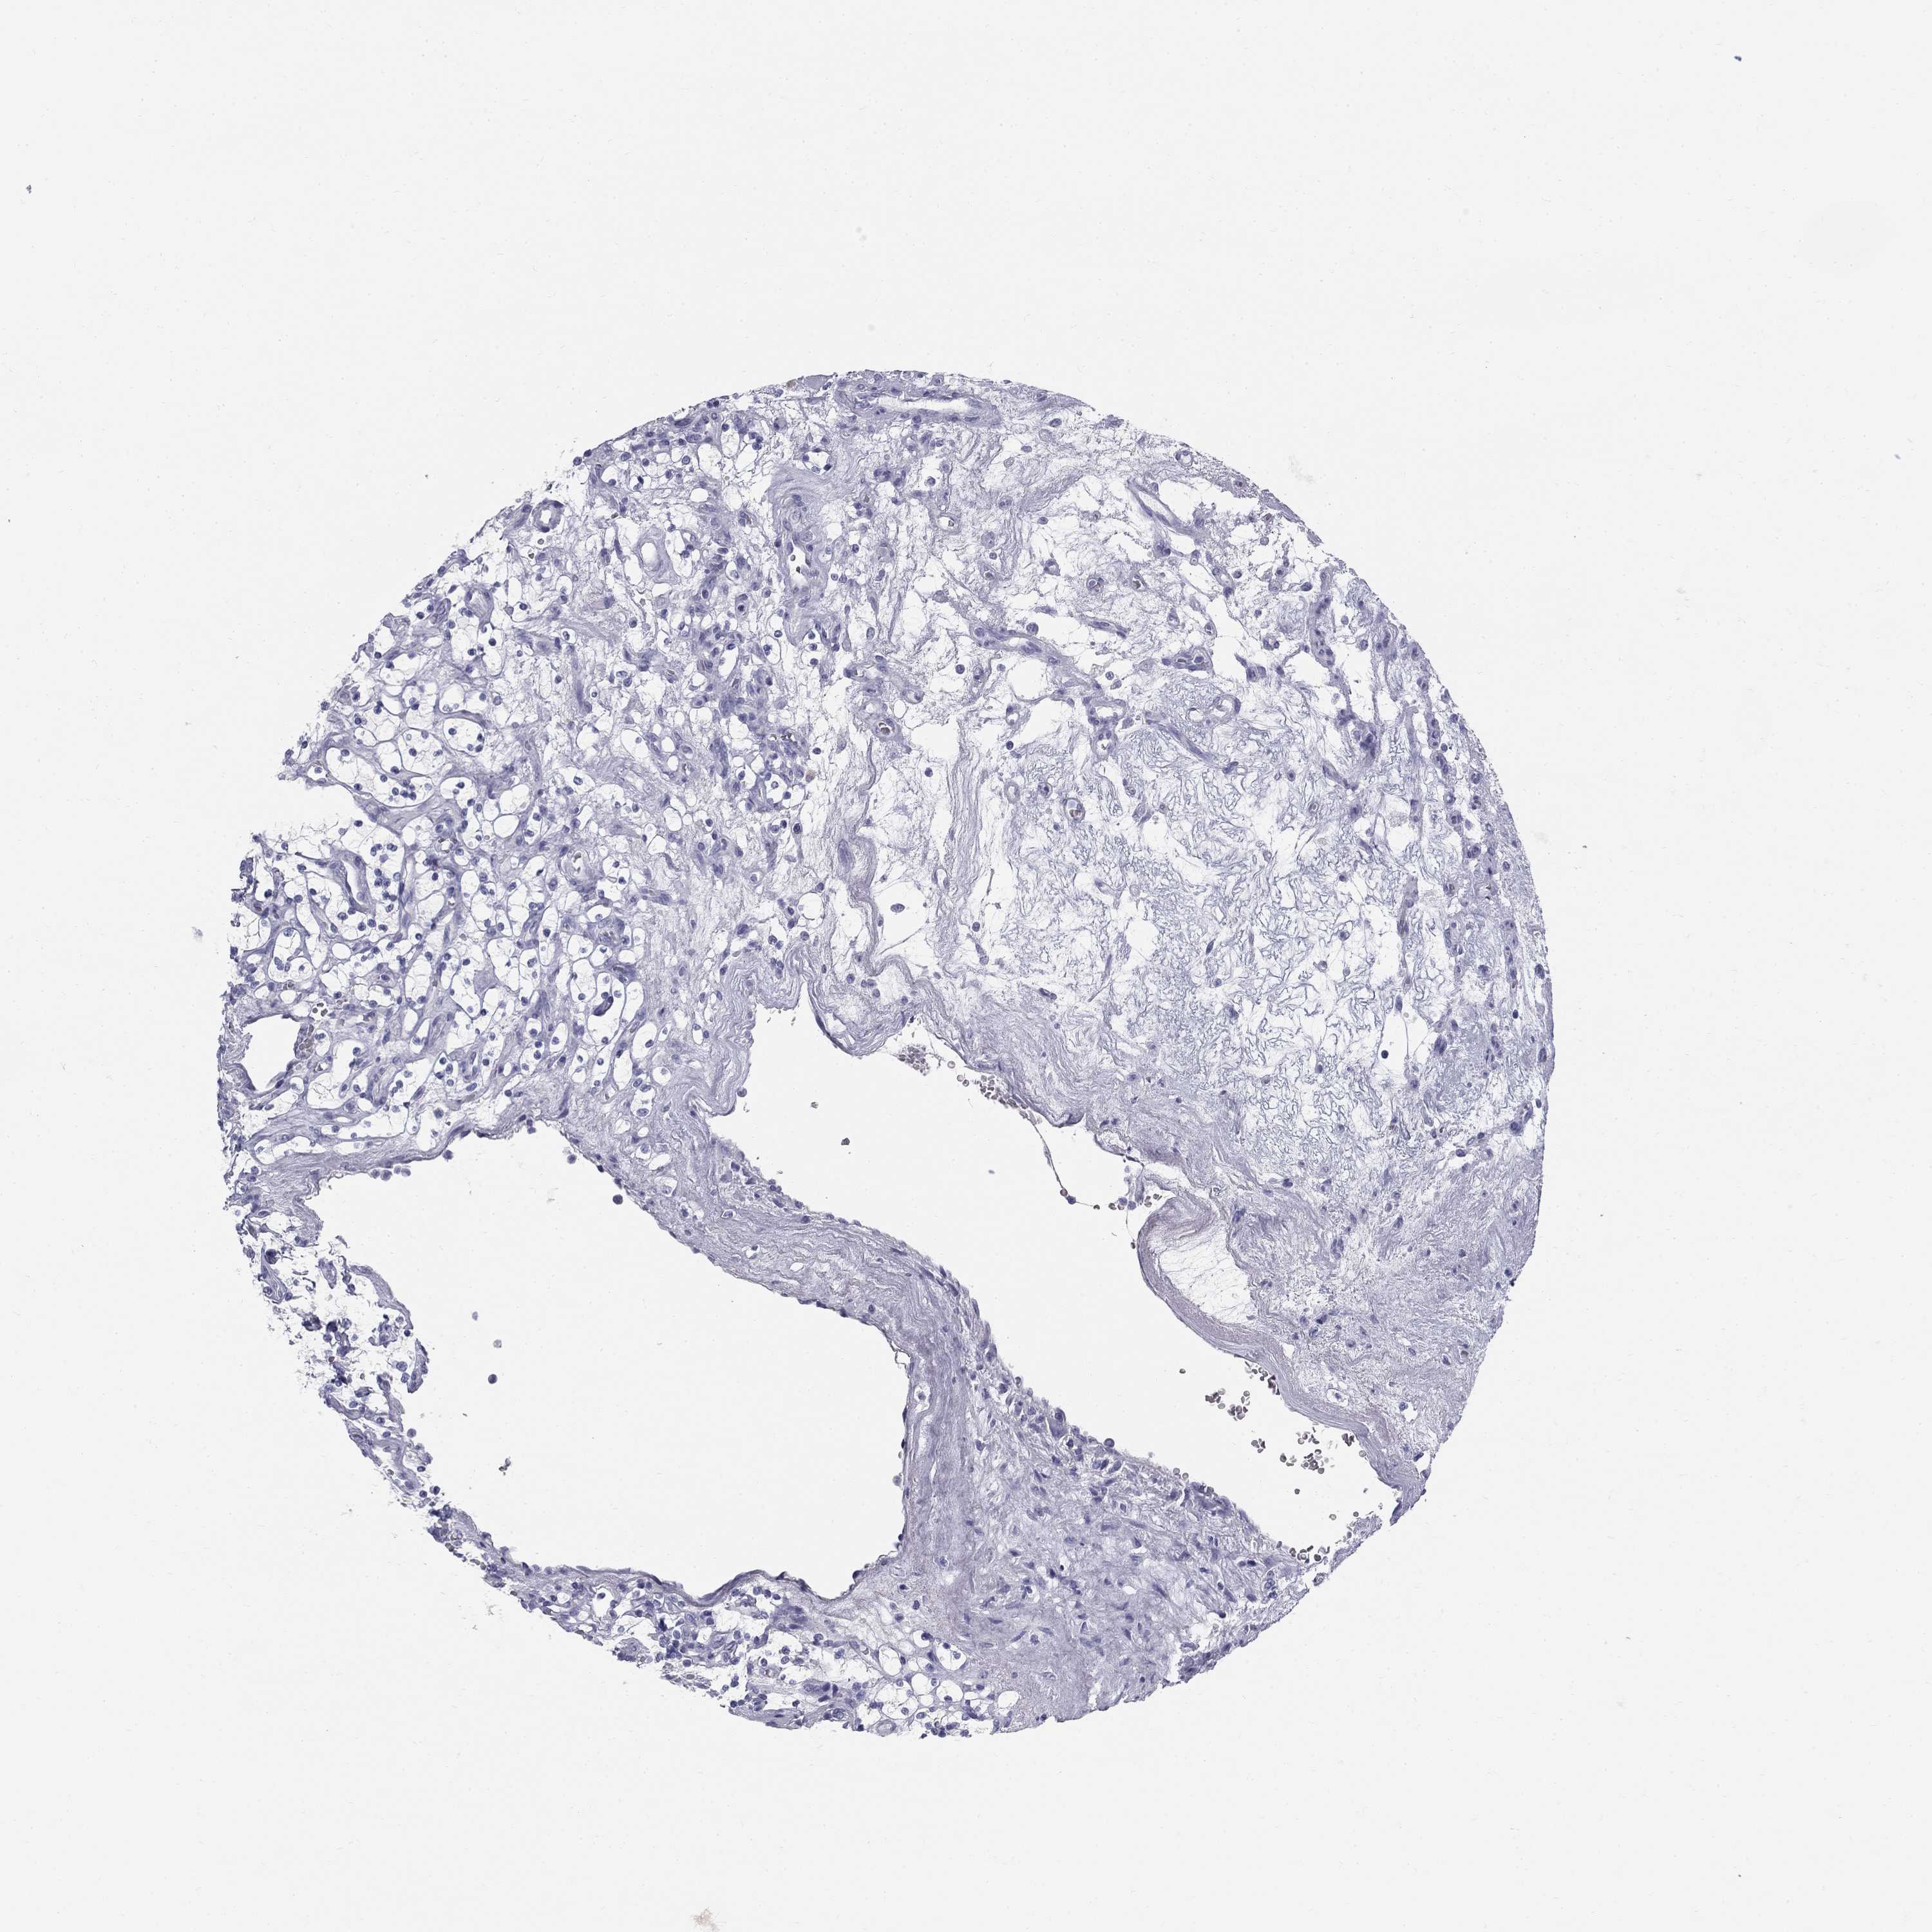

Renal cancer

Kidney renal clear cell carcinoma